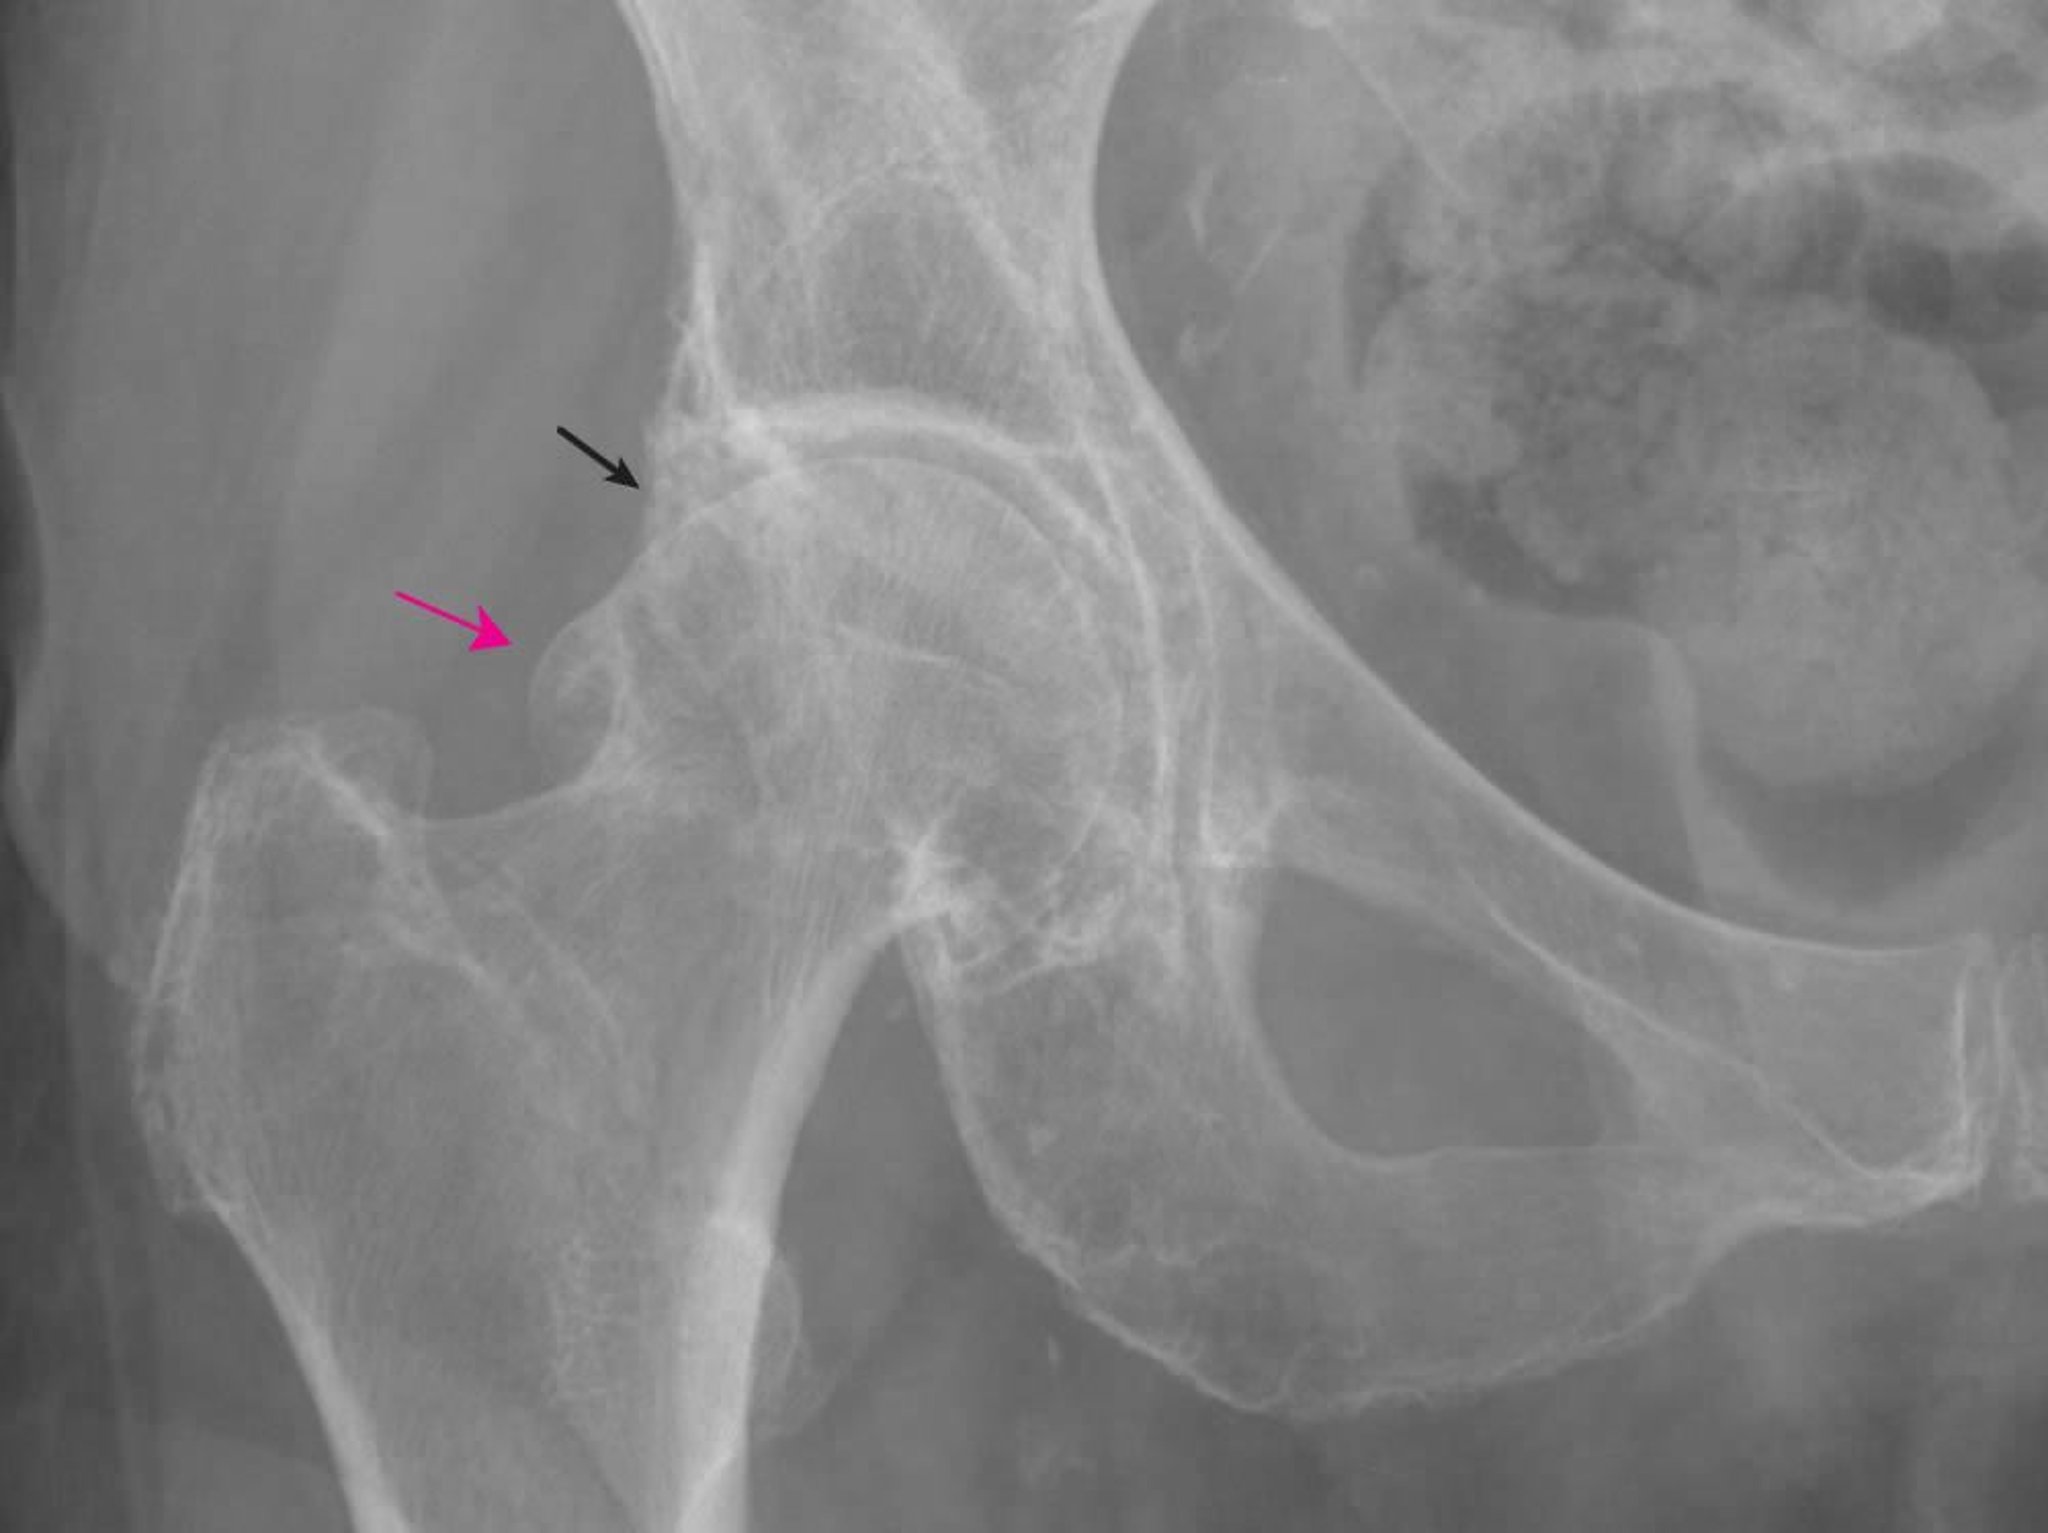

Osteoartrite do quadril

Essa radiografia mostra alterações típicas da osteoartrose, incluindo grandes osteófitos femorais (seta vermelha) e acetabulares (seta preta) e algum estreitamento do espaço articular.

Imagem fornecida por Roy Altman, MD.